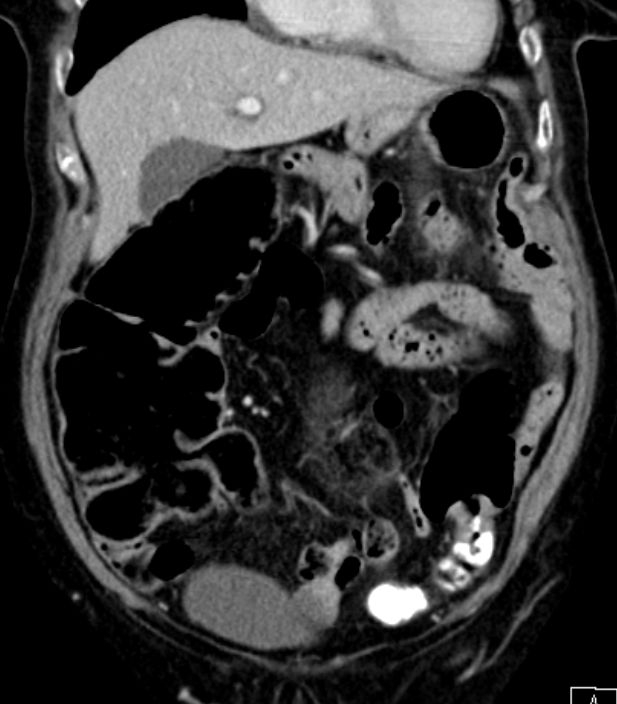

| Ileus | Das CT zeigt einen stenosierenden Sigmatumor mit ausgeprägtem Ileus. |

| Ileus | 78-jährige Frau in der Notaufnahme wegen Ileus. Tumor am deszendo-sigmoidalen Übergang. Hemokolektomie: Ulzeriertes Adenokarzinom pT3b pN1a (1/12)Mo L1 Vo. | ||